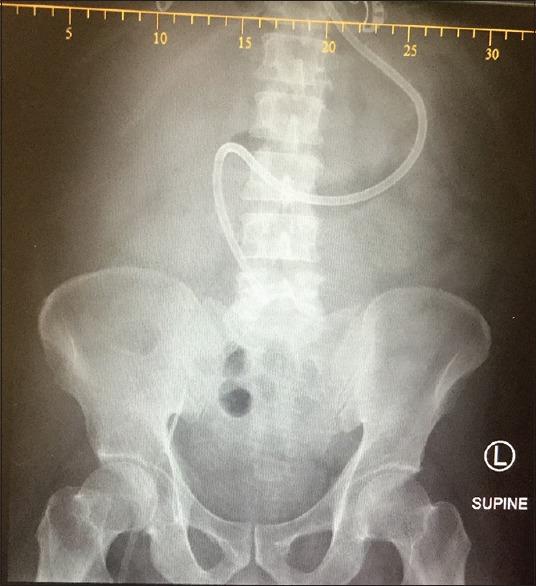

Enteral nutrition is the preferred mode of nutrition in critically ill patients whenever feasible as it has a number of advantages over parenteral feeding. Both gastric and small-bowel feeding can effectively deliver calories. In patients with gastroparesis, small-bowel feeding can help avoid parenteral feeding. We carried out a retrospective observational study to assess the ability to insert the Tiger 2 tube into the small bowel at the bedside in 25 patients who failed to tolerate gastric feeds. The time taken, rate of successful insertion, and ability to feed these patients using a standardized feeding protocol were noted. Success rate of insertion was 78% and feeding could be established. This method reduced the delays and risks associated with transportation and dependence on other specialties.

https://cdn.ncbi.nlm.nih.gov/pmc/blobs/f5c2/4922290/ec97af453899/IJCCM-20-357-g001.jpg